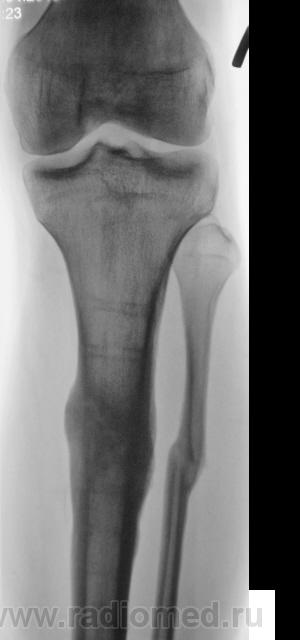

Щелевидный дефект до 1/2 d кости обусловлен, по всей вероятности, необезыствленной остеоидной тканью. Со временем "захряснет". Клиницисты в таких случаях констатируют консолидированный перелом.

СОСТОЯНИЕ КОСТНЫХ ОТЛОМКОВ УДОВЛЕТВОРИТЕЛЬНОЕ. ЛИНИЯ ПЕРЕЛОМА НЕ ОПРЕДЕЛЯЕТСЯ. ИЗБЫТОЧНАЯ КОСТНАЯ МАЗОЛЬ. А ДЛЯ ЧЕГО МСЭК?

Пациент борется "за группу" применяя все тактические дозволенные и не дозволенные действия. На мой взгляд , некоторая избыточная костная мозоль есть. Длинник кости сохранен.

Консолидированный  перелом костей голени на границе верхней и средней 1\3 диафизов. Состояние костных отломков удовлетворительное. Линия перелома, практически, не визуализируется. В б\б кости линия простветления до 1\2 поперечника, обусловленная дефектом костной ткан. Определяется избыточная костная мозоль. В верхней и средней 1\3 дефекты костной ткани как следствие перенесенной операции МОС. А на основании чего этот упорный пациент надеется получить группу?!  Все сопоставлено, срослось...  ???

Линия перелома хорошо видна на боковом снимке

Видна линия «просветения», в которой содержание солей кальция понижено. Но она не является линией перелома и пересекает не весь поперечник утолщенного диафиза. Главное: опорная функция восстановлена?